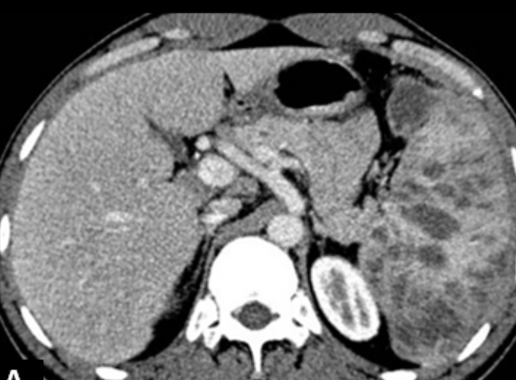

Foie et Rate

• les plus fréquents

• Nodules en hypo-atténuation

• Hepatosplénomégalie